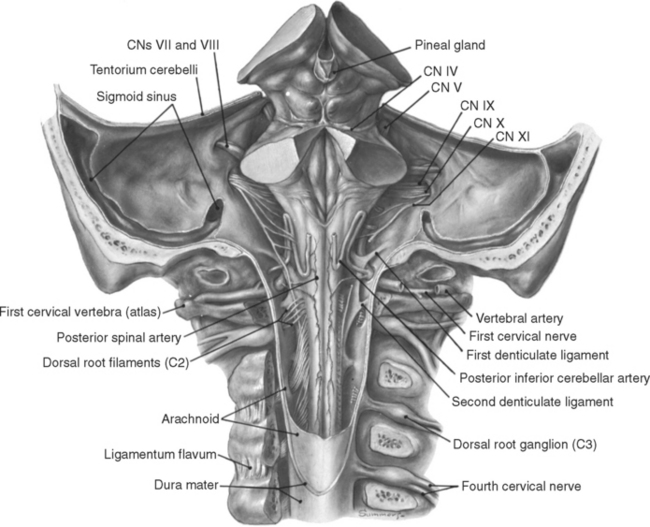

A human cervical spinal cord slice. Once you’ve read this post, you should be able to identify the major parts and tell which side is the front of the cord.

Welcome to day thirty-three in our series. For those of you who are just finding us, we have every one of these posts in our neuroanatomy category in reverse chronological order. Today we’re going to backtract (get it?) a little and go over something basic, but something we’ve skipped over to this point. We never really talked about the landmarks of a spinal cord slice. So today, we are going to take a detour and go over spinal cord features.